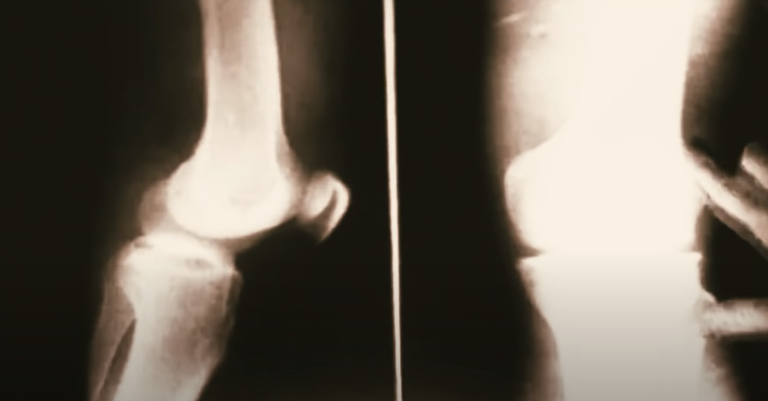

Гарринча родился с врождёнными недостатками: он страдал косоглазием, деформацией позвоночника и смещением костей таза, а его левая нога была короче правой на 6 сантиметров. Операции не помогли: врачи считали, что для ребёнка было бы просто счастьем научиться хотя бы ходить. (По другим источникам, проблемы со здоровьем у Гарринчи возникли из-за полиомиелита) Тогда никто не мог даже на мгновение предположить, что это ребёнок не просто сможет нормально ходить, но и стать одним из лучших дриблёров в истории футбола не уступая при это по скорости практически никому.